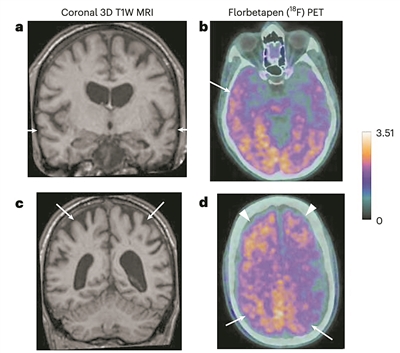

磁共振和淀粉样蛋白PET图像。图片来源:《自然·医学》

生物标志物分析在无症状时不能用于诊断阿尔茨海默病,但可以支持两名确诊患者的诊断,并表明另一人已出现阿尔茨海默病的迹象。团队还对两名研究期间去世的人做了尸检,包括大量脑组织取样,其中一名患者也显示出阿尔茨海默病的病理。